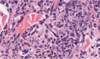

Melanoma

Dog, Horse, Angora Goat

Usually dark brown

Location, size, mitotic index, and cell morphology may help predict behavior